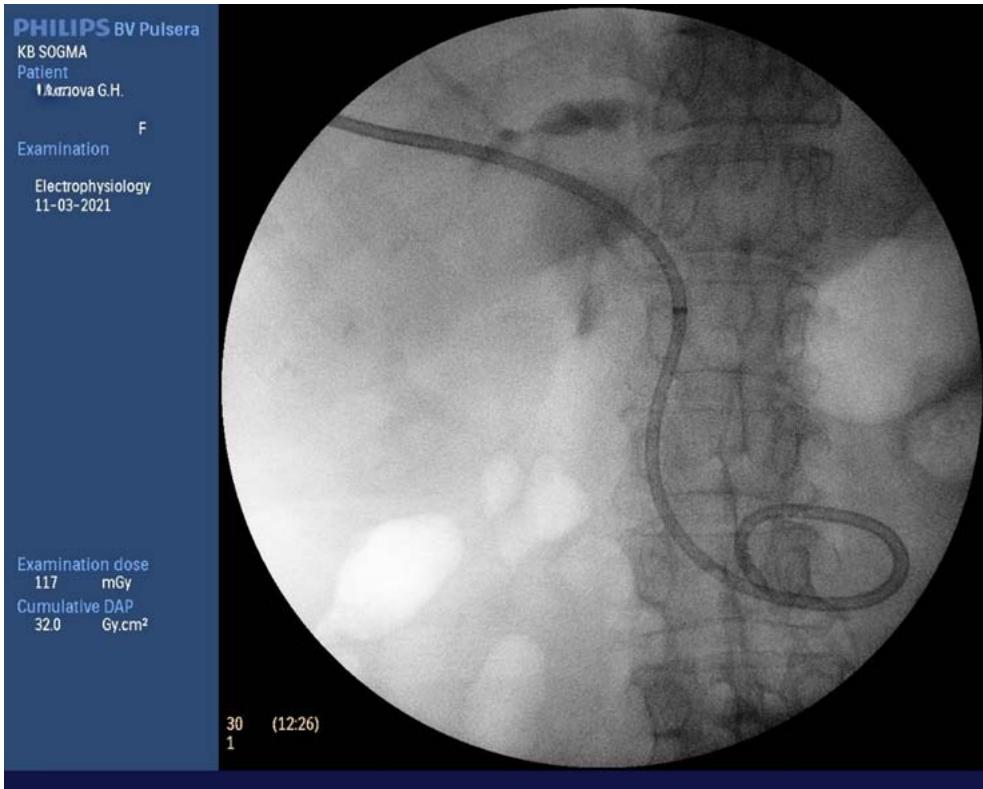

Figures 12-15 show the stages of transcholangiostomy trephine biopsy with external-internal drainage of the bile ducts and endoscopic papillsphincterotomy.

Fig. 14: External-internal drainage of the bile duct

Percutaneous transhepatic external-internal drainage of the bile ducts was performed in 266 (70,0%) patients, of which primary PTEIDBD in 57 (21,4%), the second stage after PTEDBD - in 205 (77,1%). In 4 (1,5%), it was impossible to pass the stricture area. In 14 (5,3%) PTEIDBD added with EPST. Analysis of literature data and experience in treating patients after transpapillary methods of bilioduodenal drainage allowed us to switch to primary PTEIDBD. In order to prevent postoperative pancreatitis, especially in patients with absent or mild pancreatic hypertension, external-internal drainage was supplemented with EPST. This

tactic made it possible to reduce water and electrolyte losses and shorten the length of hospital treatment.

We have developed and introduced into practical medicine method for trepan biopsy of tumours of the head of the pancreas and the distal common bile duct and device (Fig. 6)for their implementation by E.B.Revazov-Ts.S.Khutiev(patent NoNo 2722655, 2747591, 203409, 2768480). The essence of the invention is simultaneous percutaneous transhepatic external-internal drainage of the bile ducts with transcholangiostomy trephine biopsy of tumours of the head of the pancreas and the distal common bile duct and EPST (endoscopic papilla sphincterotomy) in patients with obstructive jaundice. We modified the antegrade method of core biopsy method[30] and used the principle of transjugular liver biopsy (percutaneous remote puncture biopsy with a flexible needle along a non-rectilinear trajectory with access through a tubular structure). The original deviceand method made it possible to provide trephine biopsy only under X-ray control. X-ray landmarks were the contours of the biopsy needle and metal guide (Fig.13).